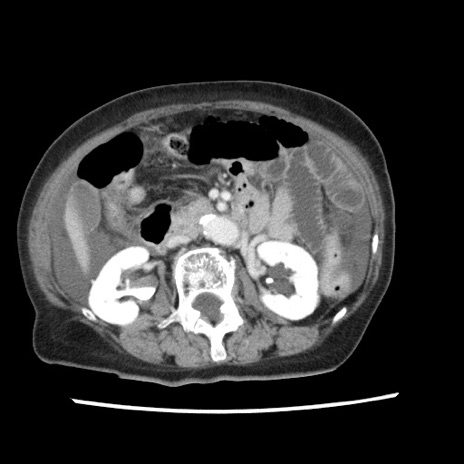

症例1(横断像)

症例

【症例】80歳代女性

【主訴】腹痛

【現病歴】8時間前から腹痛あり来院。

【既往歴】糖尿病、脂質異常症、子宮体癌にて子宮全摘術

【身体所見】意識清明・会話良好だが腹痛で苦悶様、全腹部にわたって反跳痛と圧痛あり

【データ】WBC 13600、CRP 0.14、LDH 224、CK 90